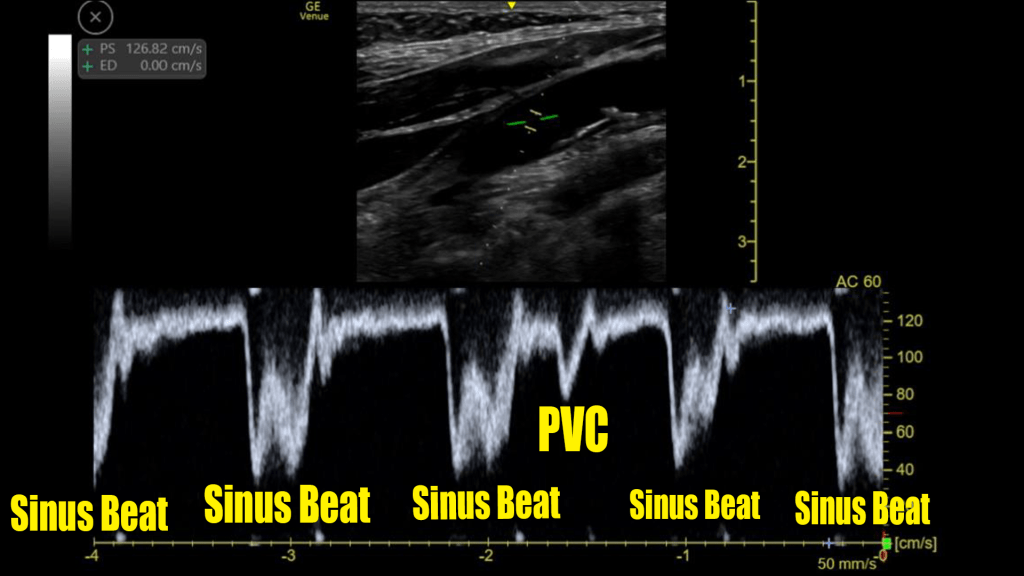

Spectral Doppler Tracing

Here we see the same patient as above. Although she was not in bigeminy at this moment, I did catch a sinus/PVC pair that was morphologically identical to those she had when she was in bigeminy.

We see that the PVC does create a forward flow of blood that is measurable in the carotid artery.